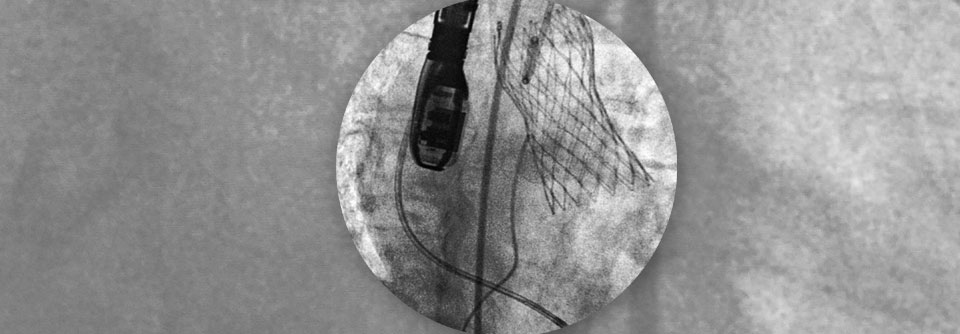

Invasive und Interventionelle Therapie

Stärkste Indikation für eine Intervention bei Aortenstenose (chirurgischer Klappenersatz oder TAVI, s. unten) sind nach wie vor die spontan oder unter Belastung auftretenden Symptome des Patienten.

Wenn Prädiktoren für eine rasche Symptomentwicklung vorliegen, kann ein frühzeitiger chirurgischer Eingriff bei asymptomatischen Patienten gerechtfertigt sein, insbesondere, wenn das operative Risiko gering ist.

Ein chirurgischer Klappenersatz wird für Patienten mit geringem chirurgischem Risiko empfohlen (STS [Society of Thoracic Surgeons]- oder EuroSCORE II < 4% oder logistischer EuroSCORE I < 10% und Fehlen weiterer Risikofaktoren wie Gebrechlichkeit, Porzellanaorta oder Folgen einer Strahlentherapie im Thoraxbereich). Eine TAVI (Transkatheter-Aortenklappenimplantation) wird für Patienten empfohlen, die für einen chirurgischen Klappenersatz nicht geeignet sind.

Die Entscheidung für einen chirurgischen Klappenersatz oder eine TAVI sollte von einem Herzteam nach umfassender, sorgfältiger Untersuchung des Patienten und unter Berücksichtigung der individuellen Risiken und des zu erwartenden Nutzens getroffen werden